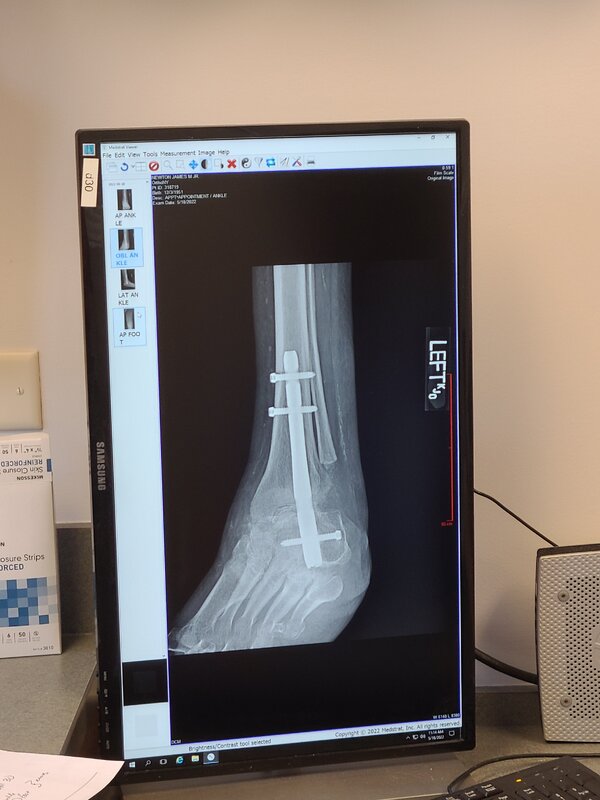

I can now get the foot wet, and I have been cleared for full weight bearing on my leg by the 10th, having gotten my cast removed, and been fitted for my new "walking boot" today.

View attachment 723378View attachment 723380View attachment 723379